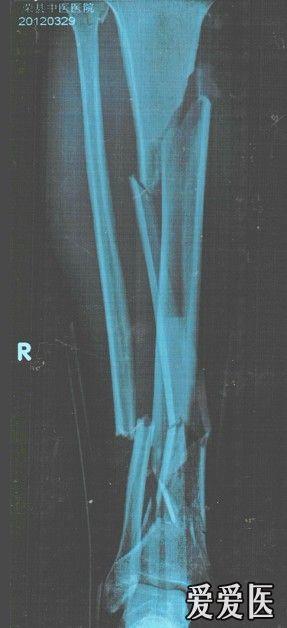

胫骨多段骨折,请大家指点一下,如何选择内固定

辅助检查:拍片:胫骨多段骨折

初步诊断:胫骨多段骨折

诊断依据:拍片:胫骨多段骨折

讨论内容:胫骨多段骨折,请大家指点一下,如何选择内固定胫骨多段骨折,请大家指点一下,如何选择内固定。